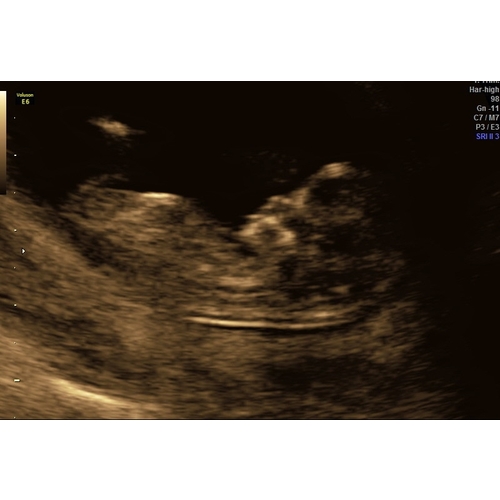

Wat denken jullie meisje of een jongetje.. spannend!

Jongen denk ik, ook de nub馃挋

Wat denk je van mijne ?